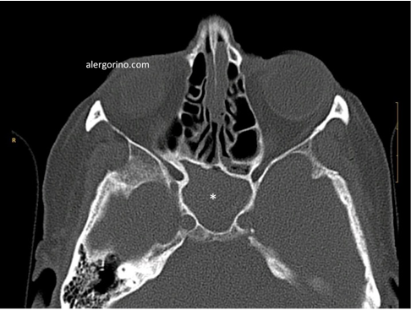

El diagnóstico se realiza mediante la historia clínica y una endoscopia nasal que proporcionan datos como la presencia de pólipos, la descarga mucopurulenta y el edema o la obstrucción de las áreas de drenaje de los senos paranasales. Si no se produjera una respuesta al tratamiento médico se evalua la situación de los senos paranasales mediante una tomografía computarizada (TC).

tomografía computarizada sinusitistomografía computarizada sinusitis tomografía computarizada sinusitis crónicatomografía computarizada sinusitis crónica